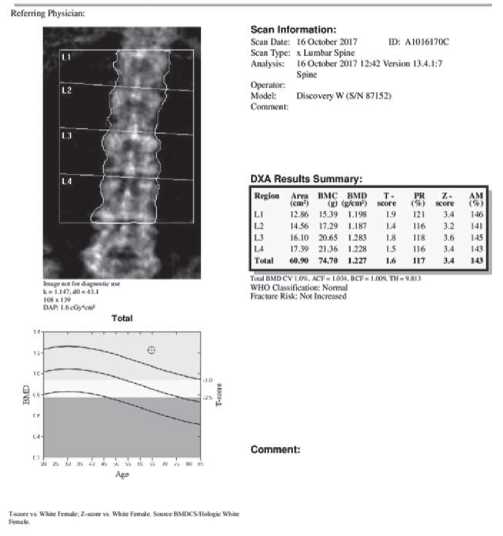

Рис. 1. Остеоденситометрия. Пациентка Т, 44 года. Область исследования: поясничный отдел позвоночника. Площадь сканируемой поверхности (Area): 60,9 см2. Содержание костного минерала (BMC): 74,7 г. Проекционная минеральная плотность костной ткани (BMD): 1,227 г/см2. Т-критерий = 1,6; Z-критерий = 3,4.

Минерализация костей поясничного отдела позвоночника — в пределах нормальных значений.